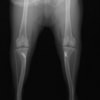

■ 症例20 ポメラニアン 8ヶ月 1.8kg

左右膝蓋骨脱臼 グレードⅢ

2ヶ月前から間欠的跛行が認められ、両膝の膝蓋骨脱臼整復術を行った。

手技は縫工筋及び内側広筋の解放、脛骨粗面の外側転位、滑車ブロック形造溝術、内外側関節包の縫縮を選択し実施した。

右側の膝蓋骨脱臼は上記手技で整復されたものの、左側はそれのみでは膝蓋骨が浮く様子が認められた。その為、PDS縫合糸にて膝蓋靱帯を1糸のみ縫合し、靱帯の縫縮を行った。

膝蓋骨脱臼は膝関節における膝蓋骨の内外側の脱臼と定義されるが、時として単純な内外の脱臼ではなく、膝蓋骨が大きく前方に浮き上がるように脱臼する場合がある。特にトイプードルやポメラニアンといった犬種に多く認められる。

内側脱臼に加えて前方への浮き上がりを矯正する為に、従来より脛骨粗面転移により膝蓋靭帯を外方と下方に引っ張り、固定する方法を選択する。膝蓋骨の前方への浮き上がりが軽度の場合は、従来法ではなく関節包の縫縮で対応していた。しかし、一部の症例で膝蓋骨の動きが悪くなり伸展機構が円滑に機能せずロボット様歩行になるケースがあった。

その為、膝蓋靭帯自体を縫縮する方法を採用した。この方法により、膝関節の伸展機構を妨げず膝蓋骨の軽度の浮きを矯正することが可能となった。

本症例の経過は良好である